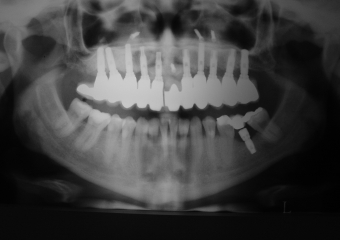

Raio X inicial